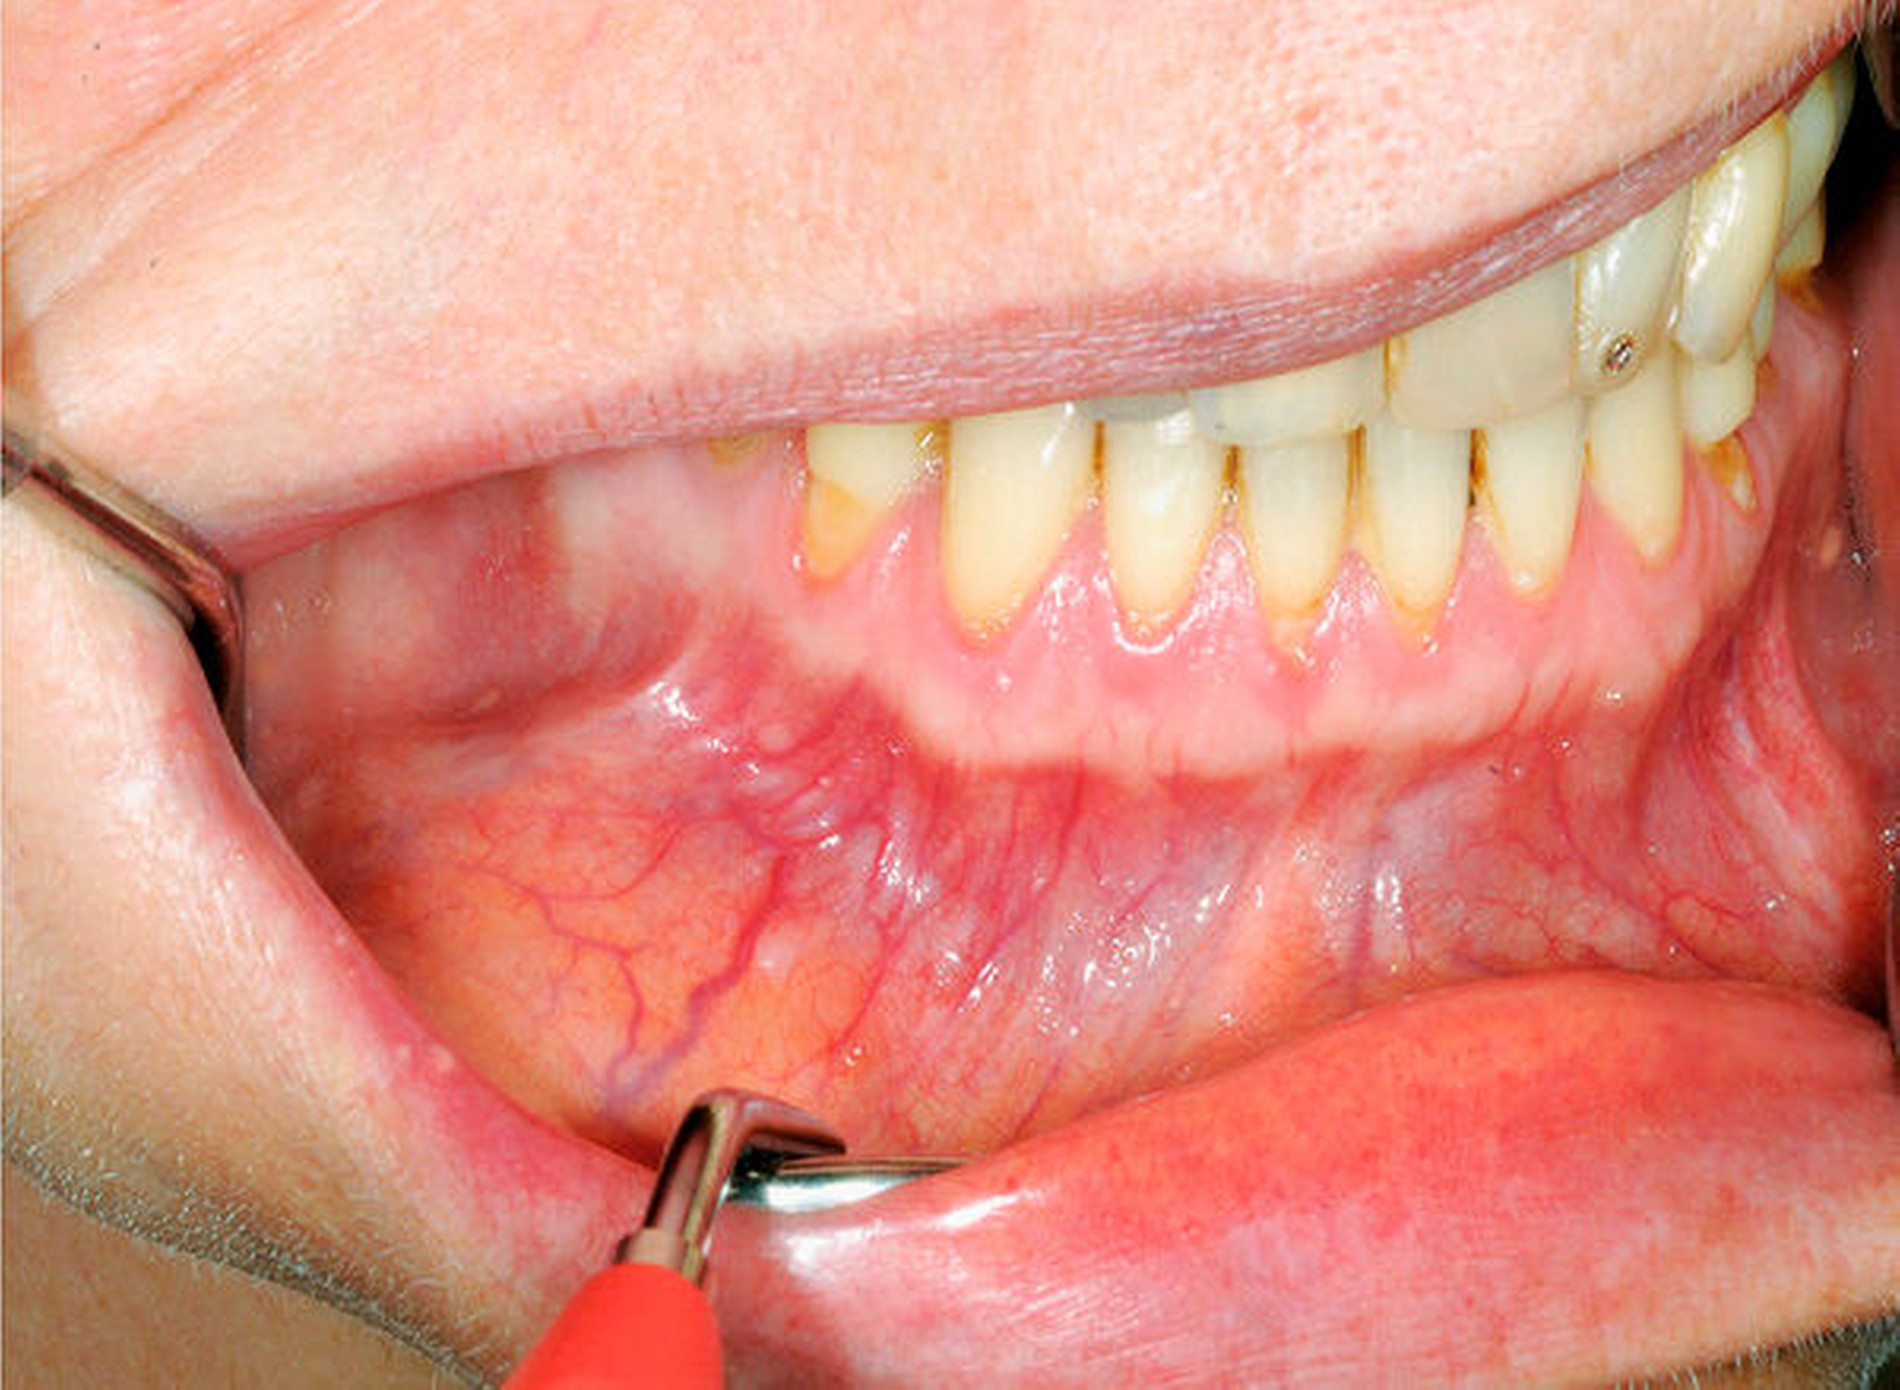

Die extraorale Untersuchung ergab eine dezente Schwellung paramandibulär rechts (Abbildung 2). Enoral war eine umschriebene, prallelastische, schmerzlose Auftreibung des Corpus mandibulae vestibulär regio 43 bis 46 zu verzeichnen, ohne akute Entzündungszeichen (Abbildung 3) bei ansonsten unauffälligem Schleimhautbefund und weitestgehend saniertem Zahnstatus. Hinweise auf eine Fraktur des Unterkiefers oder Hypästhesien ergaben sich nicht.